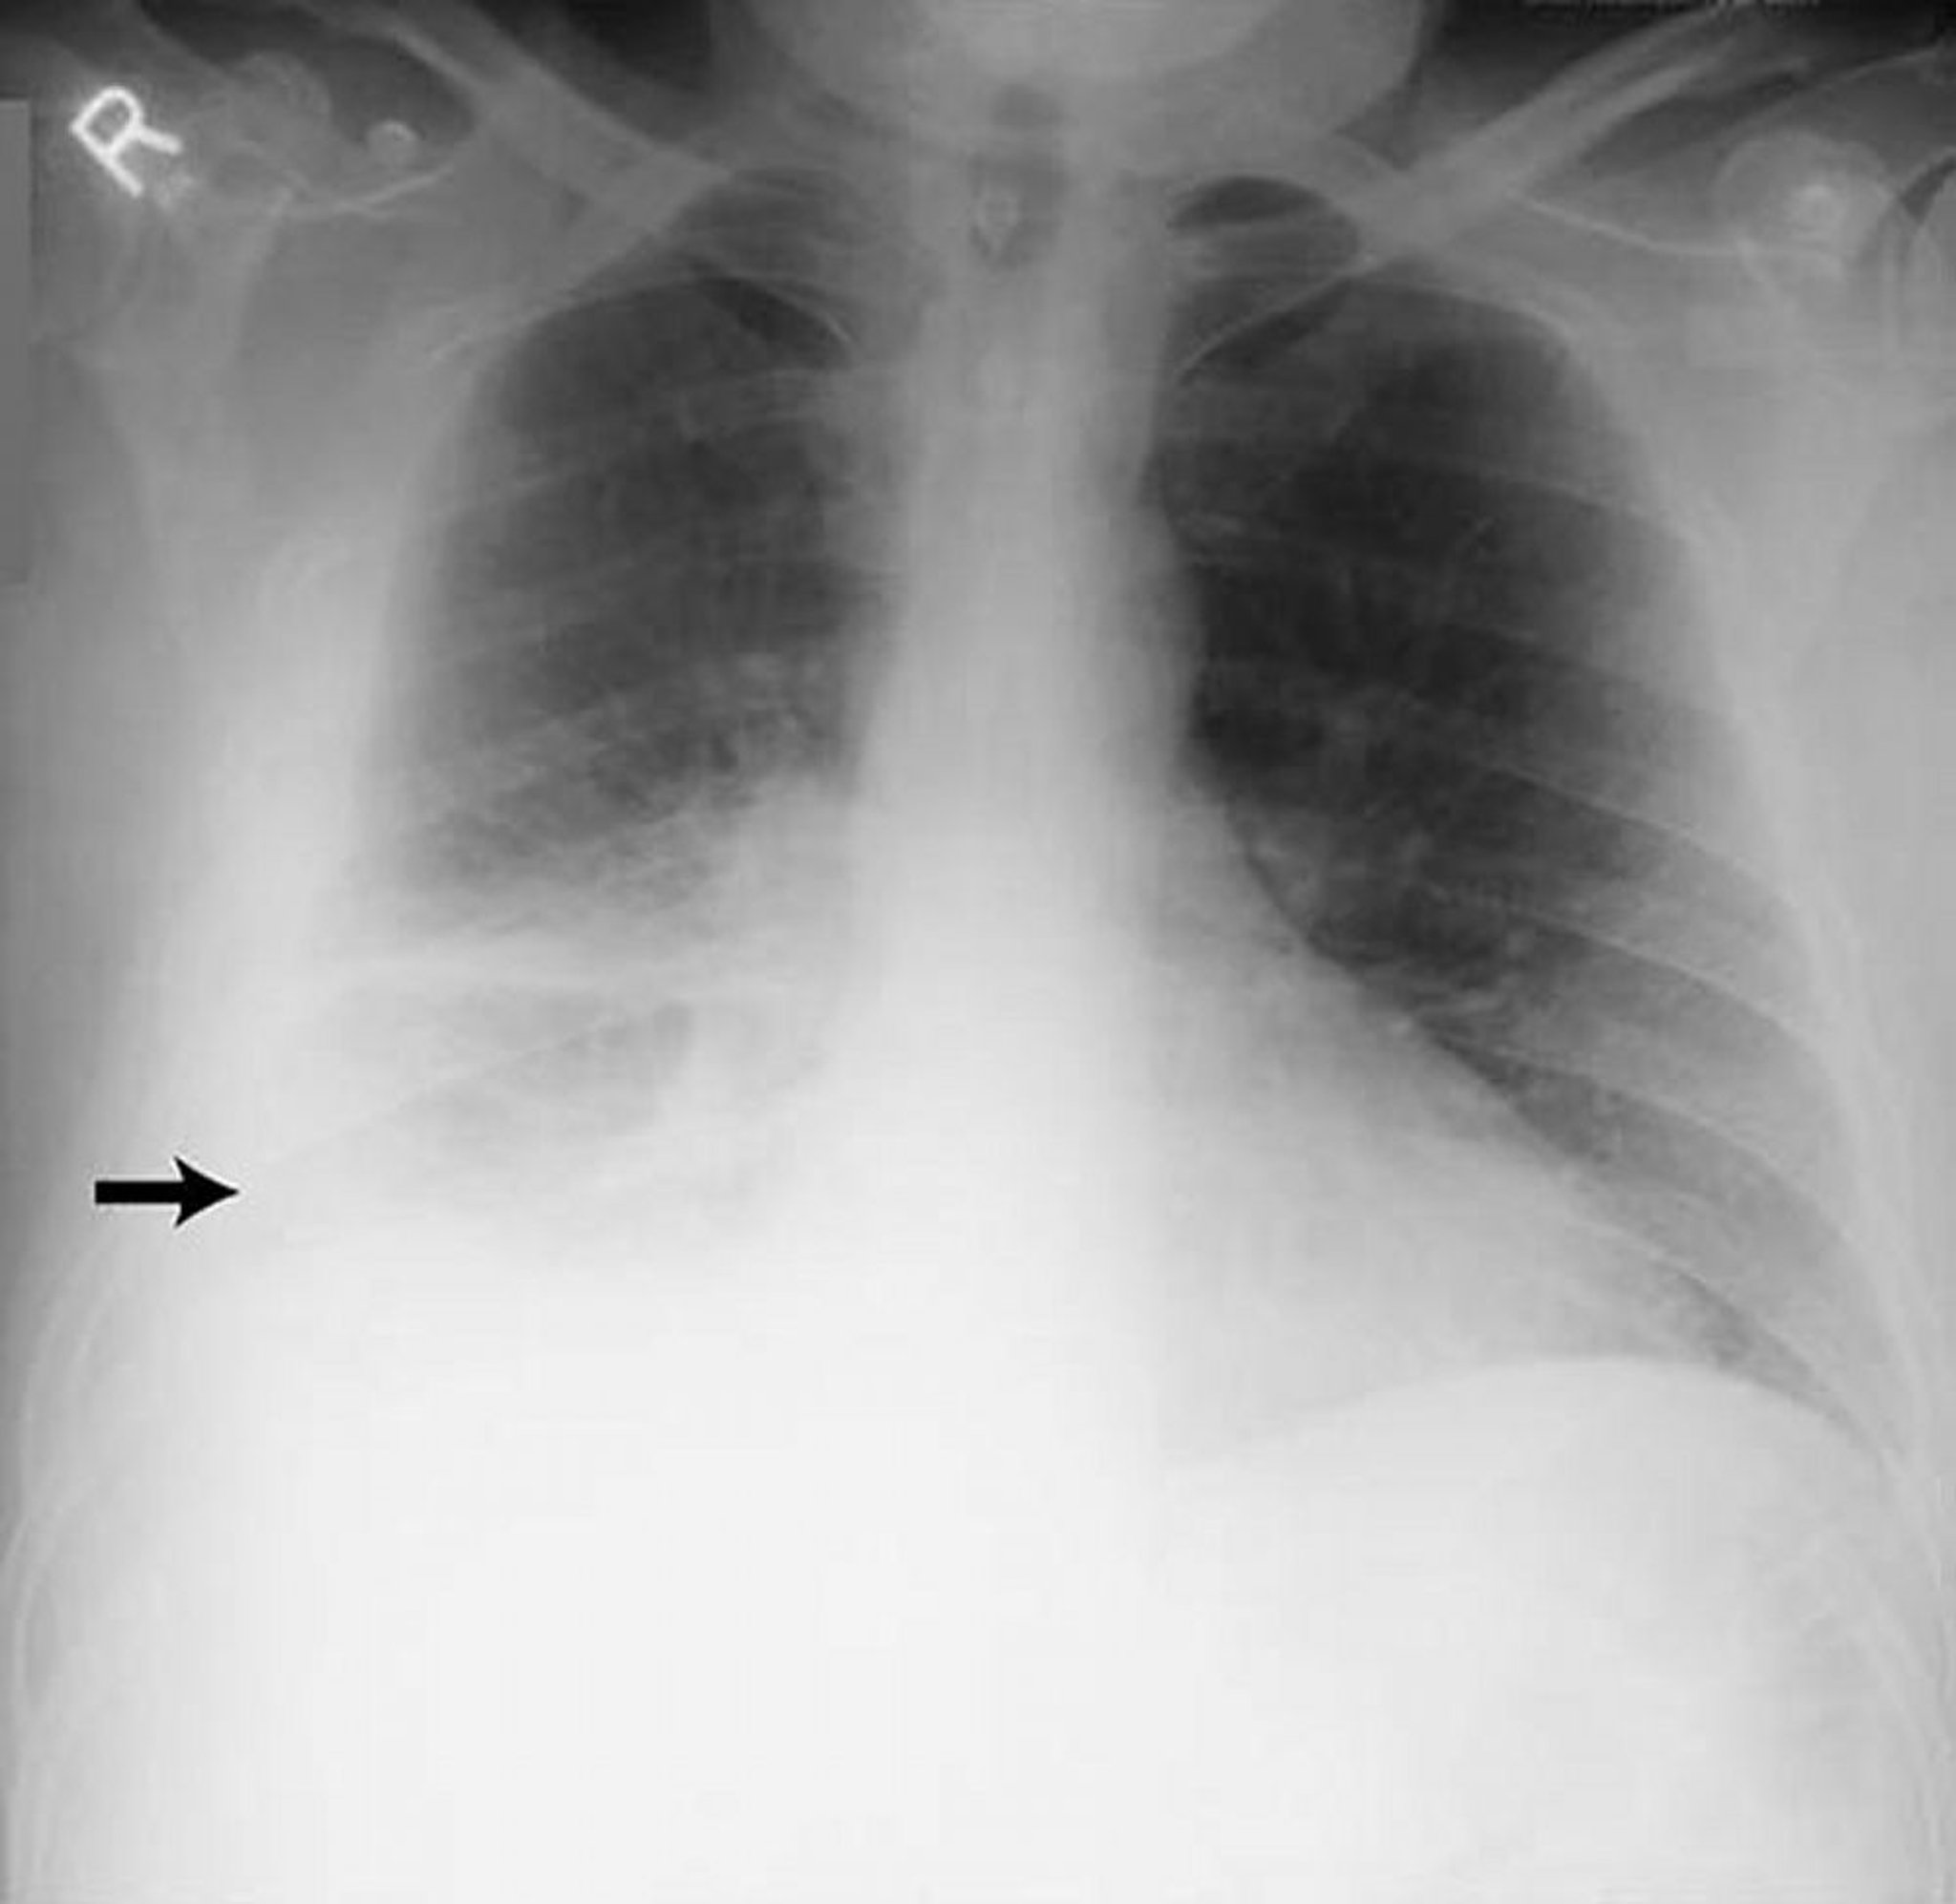

Наявність випоту

Chest radiograph is the first test performed to confirm the presence of pleural fluid. The lateral upright chest radiograph should be examined when a pleural effusion is suspected. In an upright radiograph, 75 mL of fluid blunts the posterior costophrenic angle. Blunting of the lateral costophrenic angle usually requires about 175 mL but may take as much as 500 mL. Lateral decubitus radiographs (with the side of the effusion down) may be able to detect small fluid volumes more easily than standard upright radiographs, particularly with a free-flowing effusion. Larger pleural effusions opacify portions of the hemithorax and may cause mediastinal shift; effusions > 4 L may cause complete opacification of the hemithorax and mediastinal shift to the contralateral side.

Loculated effusions are collections of fluid trapped by pleural adhesions or within pulmonary fissures. Further imaging (lateral decubitus radiographs, chest CT, or ultrasound) should be performed if it is unclear whether a radiographic density represents fluid or parenchymal infiltrates or whether suspected fluid is loculated or free-flowing; these tests are more sensitive than upright radiographs and can detect small fluid volumes. Loculated effusions, particularly those in the horizontal or oblique fissure, can be confused with a solid pulmonary mass (pseudotumor). They may change shape and size with changes in the patient’s position and the amount of pleural fluid.